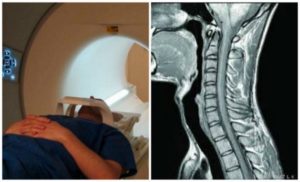

МРТ, или магнитно-резонансная томография – это способ исследования внутренних органов и, что важно при остеохондрозе, тканей с помощью магнитного ядерного резонанса.

Именно такой способ диагностики более предпочтительный на ранних стадиях болезни и для профилактики, чтобы проверить свое здоровье. Он показывает более полную картину при малейших изменениях в тканях, мышцах.

А что происходит при процессе разрушения межпозвоночного диска? Начинается воспалительный процесс в окружающих его тканях. МРТ способна показать начинающееся воспаление и позволить «схватить» болезнь на самой ранней стадии, предотвращая страшные последствия.

Магнитно-резонансная томография является единственным методом, позволяющим увидеть патологические и структурные изменения в шейных позвонках, а также оценить патофизиологические и физико-химические процессы в шейном отделе позвоночного столба. МРТ шейного отдела показывает в трехмерном изображении нервные стволы и сосудистую сеть позвоночника.

МРТ шеи обладает высоким качеством, поэтому считаются одной из лучших диагностических процедур. Оно не является альтернативной заменой компьютерной томографии, так как у этих методик разное назначение.